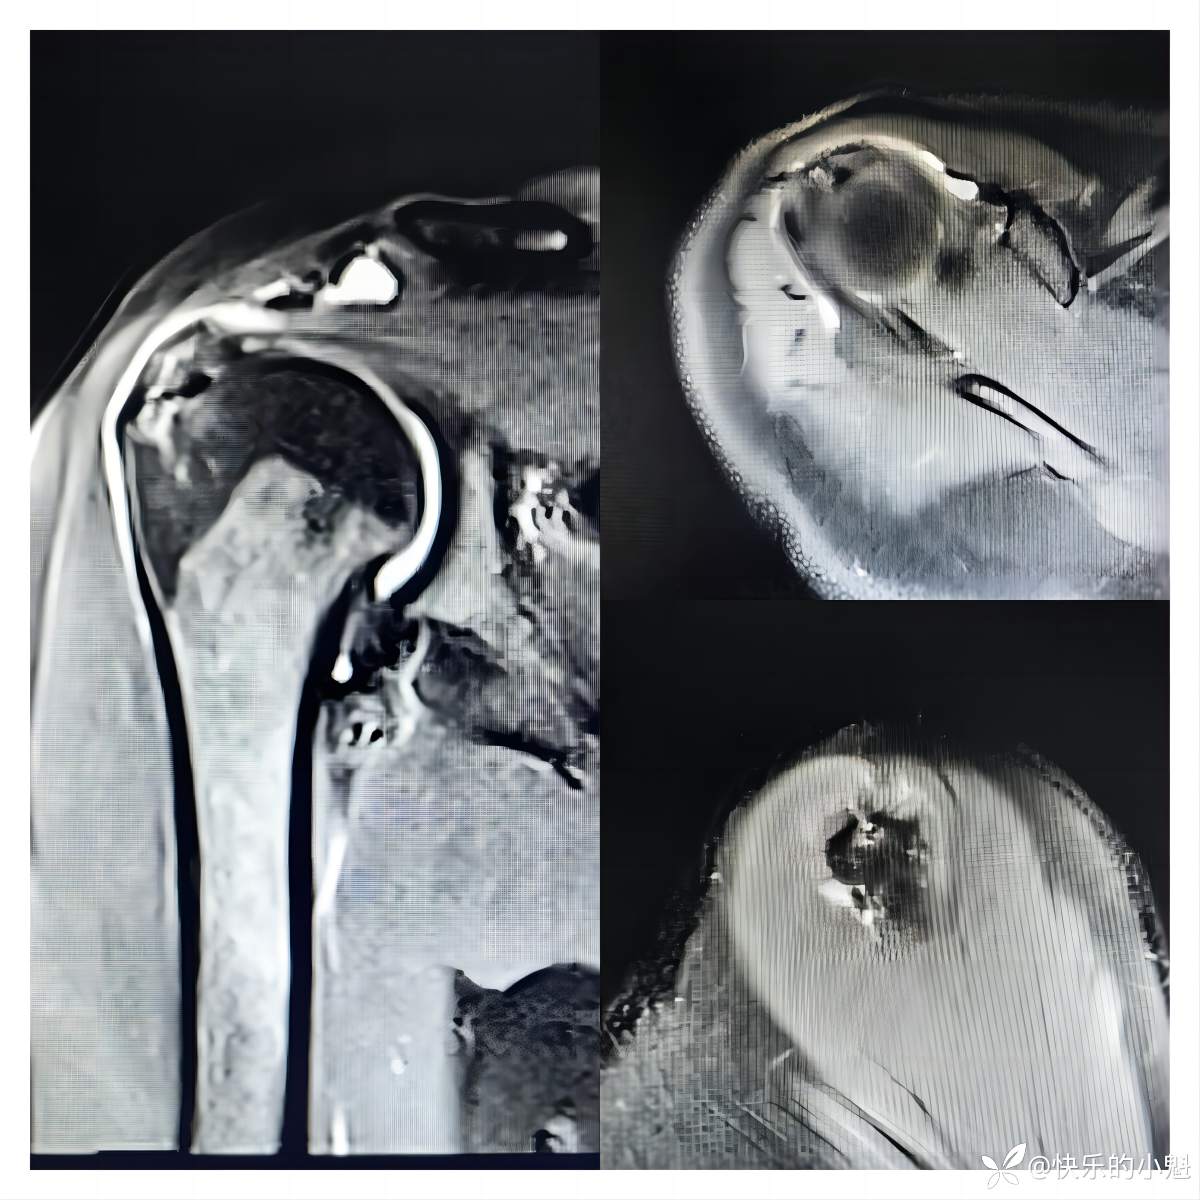

- 右肩核磁示:右侧肱骨异常信号,骨髓水肿可能,请结合临床;右侧冈上肌肌腱连续性欠佳,局部异常信号,断裂不除外,请结合临床及其他检查;右侧肩关节腔及部分滑囊积液(见下图)。